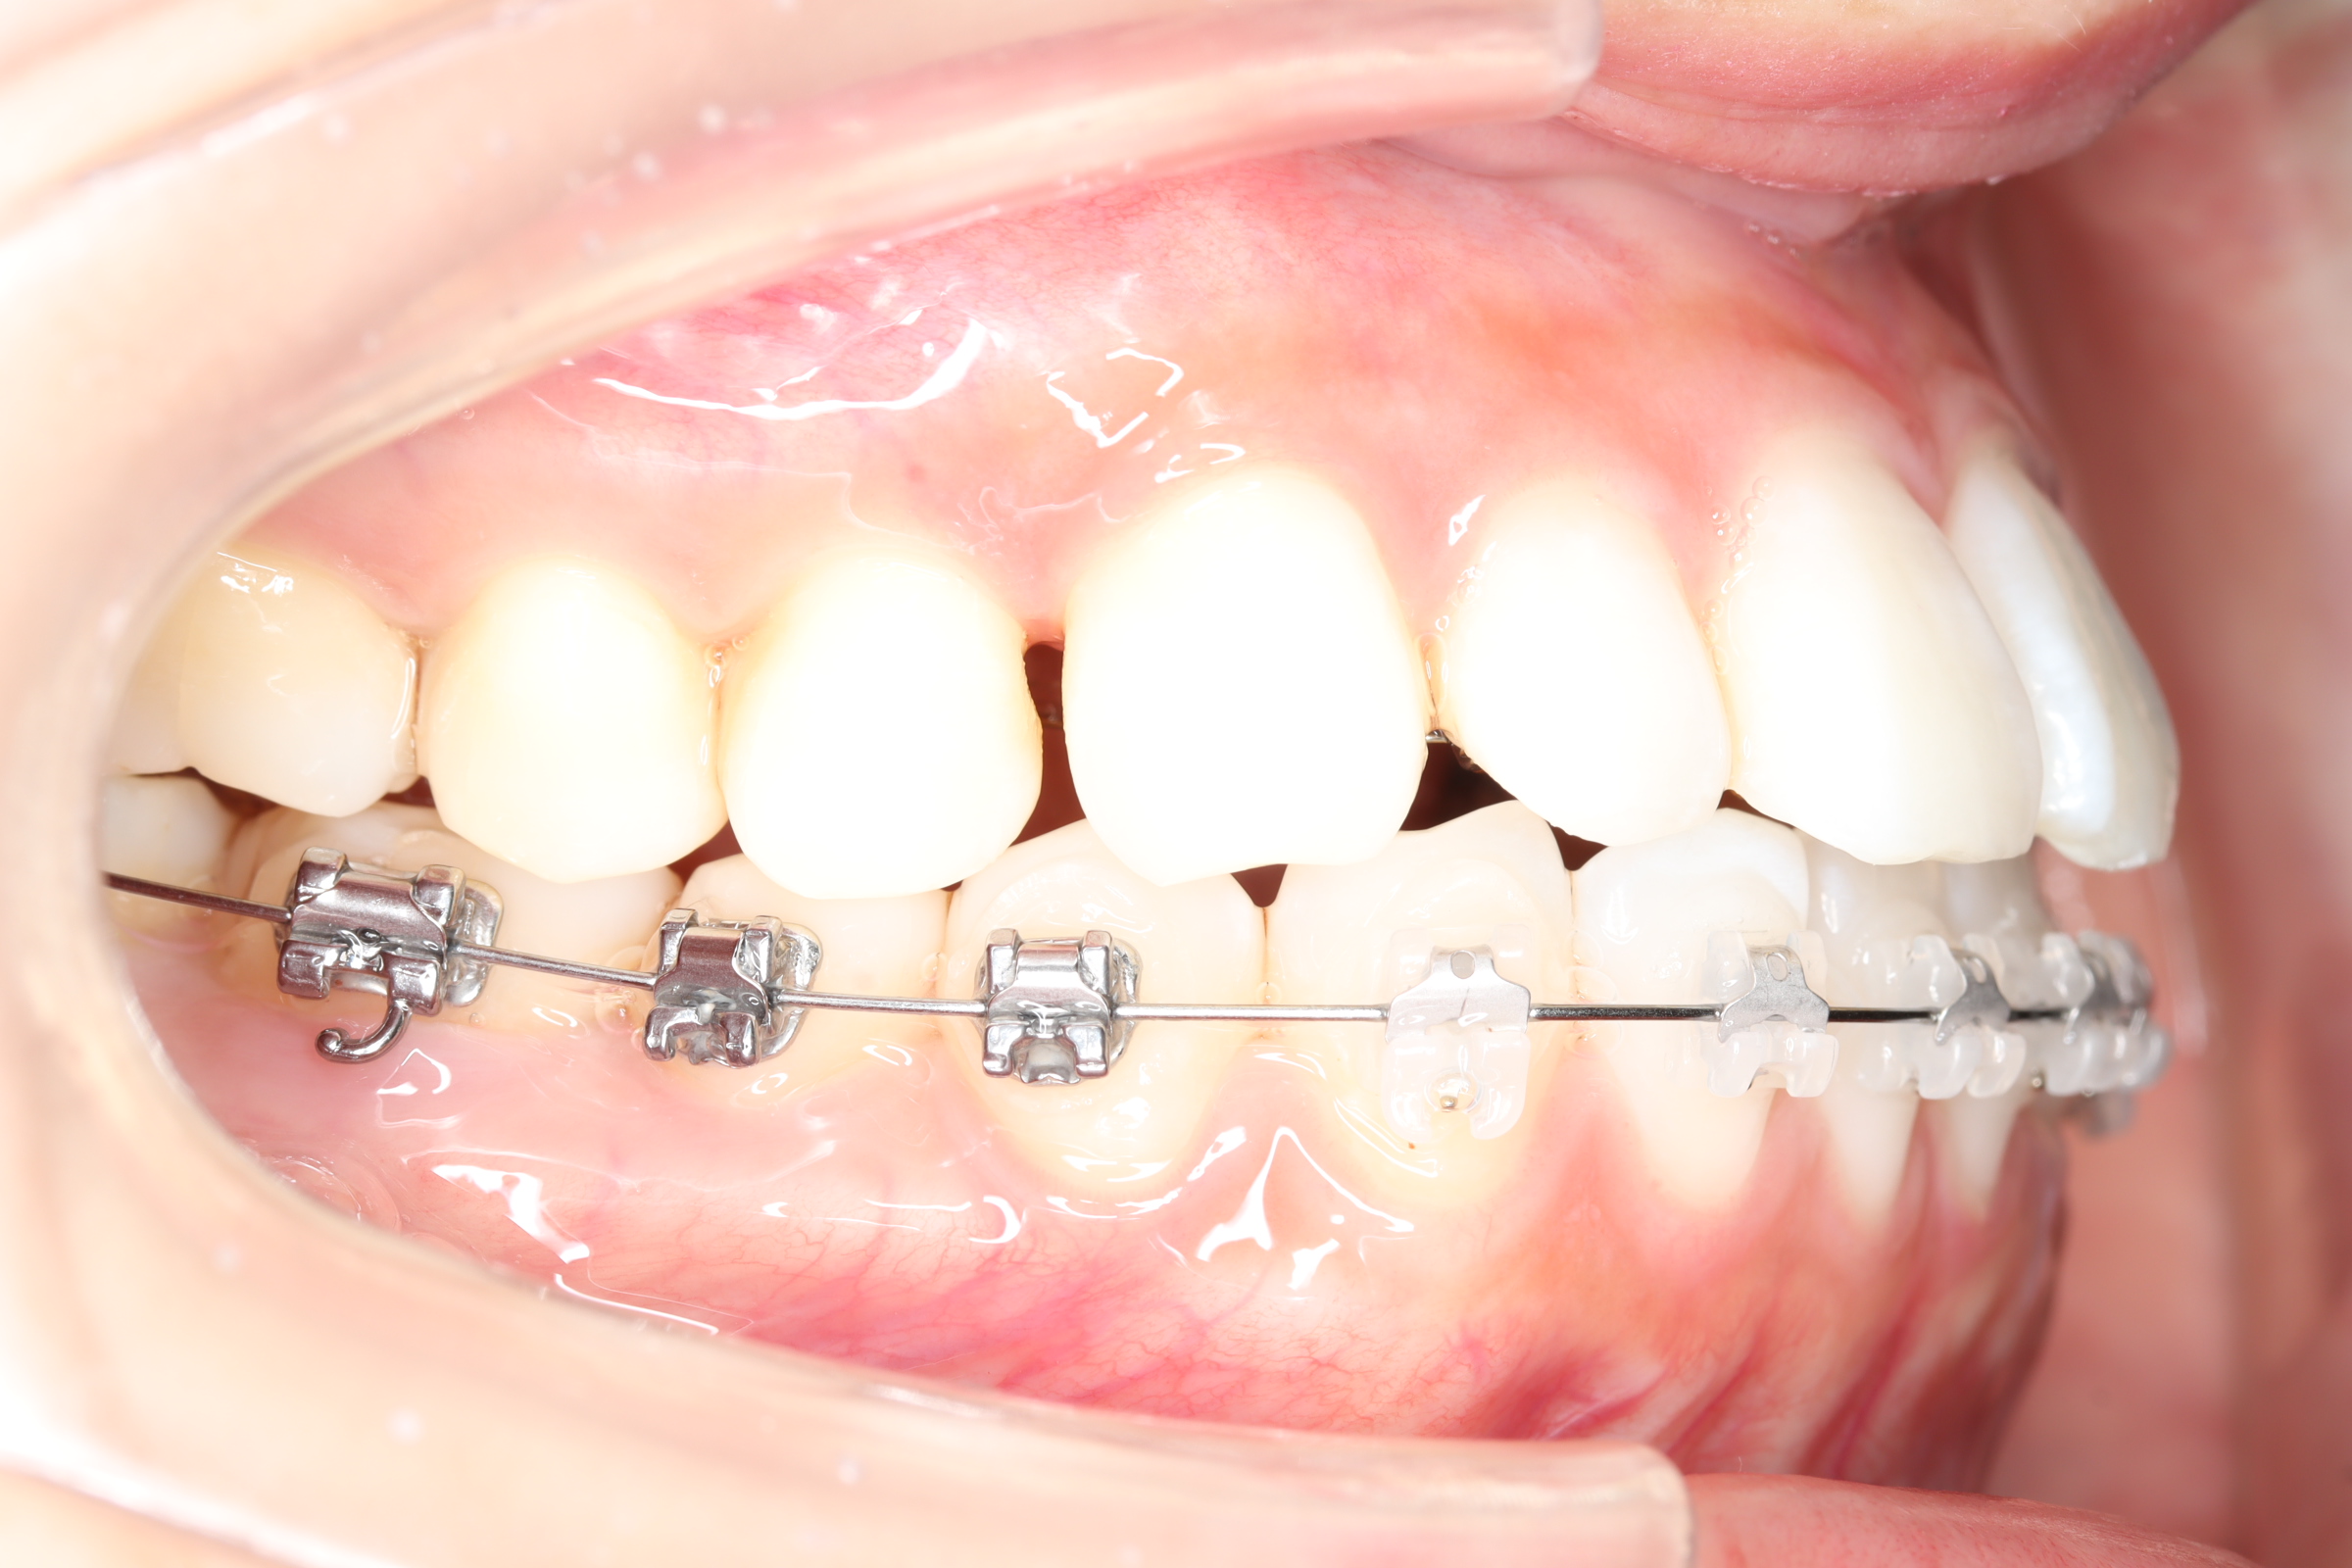

治療中

![]() | ||

| 使用矯正装置 | 上顎:セルフライゲーションリンガルブラケット 下顎:セルフライゲーションブラケット(セラミッククリッピー) 歯科矯正用アンカースクリュー |

| 想定されるリスク | 治療期間中に起こりうる関連症状として、痛み、歯根への影響、口腔内不潔域の拡大(装置の種類による)、顎関節症状、後戻り・加齢による変化などが挙げられます。 |